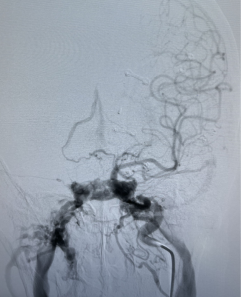

神经外科血管病团队立即为患者进行脑血管造影,分别对颈内动脉、颈外动脉、椎动脉进行造影,同时进行压颈试验,评估血管代偿情况,得出结论:左侧颈内动脉海绵瘘,瘘口流量大,3D旋转不能显示瘘口,向两侧颈内静脉引流,左侧眼静脉粗大,左侧岩下窦显影,前交通动脉代偿良好,后交通动脉代偿差。

全科讨论手术方案后,一致认为要栓塞瘘口并保护好左侧颈内动脉的通畅,遂决定采用静脉途径使用“钢筋混泥土”(同时使用弹簧圈和液体栓塞剂)结构牢牢堵住瘘口。

3月16日13点,张卫东带领团队为患者行颈内动脉海绵窦瘘栓塞术,同时行股动脉、股静脉穿刺,微导管翻山越岭后进入海绵窦。为确保左侧颈动脉不受干扰,于颈动脉内置入球囊予以保护。

在团队的协作下,经过2个多小时惊心动魄的战斗,堵塞瘘口的“钢筋混泥土墙”终于修好啦。

(栓塞术前,瘘口流量大,深部静脉危险引流)